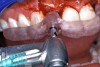

Figure 15a  A surgical template was derived from the final treatment plan created in the software, which facilitated (A) the drilling sequence and (B) precise location of placement.

Figure 15a

Figure 15b  A surgical template was derived from the final treatment plan created in the software, which facilitated (A) the drilling sequence and (B) precise location of placement.

Figure 15b

Before the day of surgery, the patient was seen by the orthodontist for the removal of the orthodontic brackets. The patient still was not pleased with the position of the two centrals, and it was determined that this would be addressed after implant placement (Figure 13A). The anatomical variations of the crestal tissue and lack of interdental papilla can be appreciated in the close-up views of the right and left sites (Figure 13B and 13C). There were no surprises on the day of surgery as all of the decisions were made during the planning phase, before the scalpel ever touched the patient. The occlusal view of the CT 3D model revealed the wider alveolar ridge on the right side and thinner crest on the left side (Figure 14A). This was confirmed when the full thickness mucoperiosteal flaps were elevated, and the underyling bone revealed (Figure 14B). The tooth-borne templates were designed to facilitate the drills and drilling sequence specific to the diameters of the predetermined implants (Figure 15A). Each template contained an embedded 5-mm long stainless steel tube, which was approximately 0.2-mm wider than each drill (just wide enough to allow for the drills to rotate freely). Once positioned over the natural teeth, the template was secure and offered precision accuracy in transferring the implant locations from the original software-designed plan, allowing the potential for internal and external irrigation (Figure 15B). The 3.7-mm diameter Tapered Screw-Vent implant drilling sequence requires three drills: pilot, intermediate, and final sizing. Thus, three separate templates were fabricated to a.commodate these sizes. The templates were removed easily and replaced with the next sequential size in less time than it takes to change the drill on the surgical handpiece. After the osteotomies had been.completed, the implants were delivered to the site (Figure 16A and Figure 16B). For this internal hex connection implant, the author r.commends that the flat of the antirotational hex be positioned to the facial for proper orientation of the restorative.components (Figure 17A). Preprepared margins were created from a milled titanium fixture mount transfer post, which was delivered to the implant as support for an immediate transitional restoration. The facial “dot” helped confirm the orientation of the abutment to the facially positioned flat side of the internal hex connection (Figure 17B). Before cementation of the transitional acrylic restorations, a closed-tray, fixture-level impression was made, and a soft-tissue model fabricated.